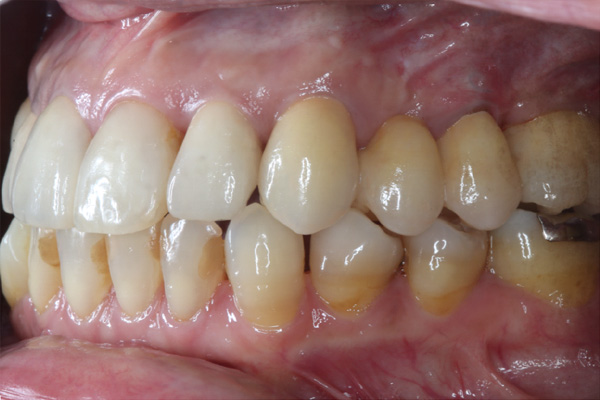

| 年代・性別 | 50代 男性 |

|---|---|

| 主訴 | 右下の歯が割れてしまったのでインプラントをして欲しい |

| 治療期間 | 約6ヶ月 |

| 費用 | 1,100,000円 |

| 治療内容 | インプラント、骨造成、結合組織移植、セラミック修復 |

| 治療に伴うリスク | インプラント周囲炎 セラミックの破折、脱離 |

*キャンセルポリシーをご一読のうえご予約ください